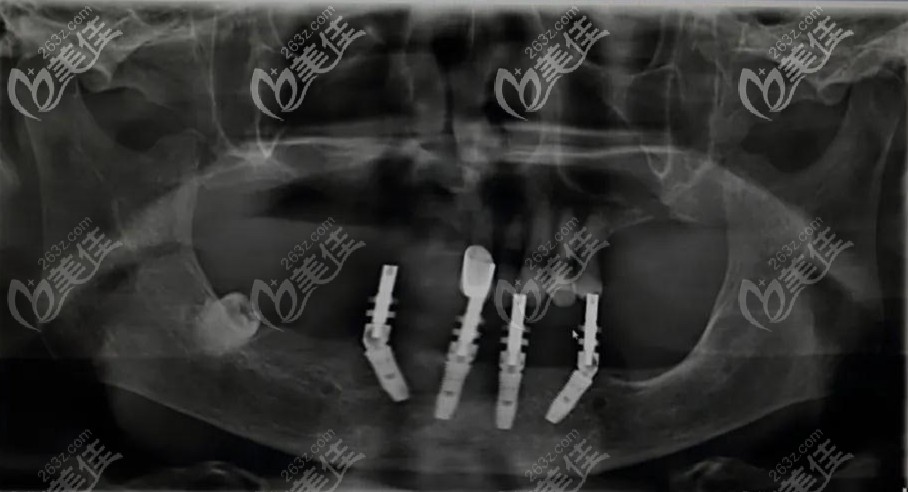

運用口腔CBCT掃描,獲取缺牙的位置、牙骨高度、咬合關(guān)系、密度等數(shù)據(jù),360°觀察和分析病例,不放過任何一個細節(jié)問題。

使用3D打印種植體定位導(dǎo)板精準(zhǔn)的植入種植體,有效避開神經(jīng)和血管,8分鐘就能種植一顆牙。

用登騰做全口allon4即刻負(fù)重種植牙讓林大伯當(dāng)場就能啃蘋果